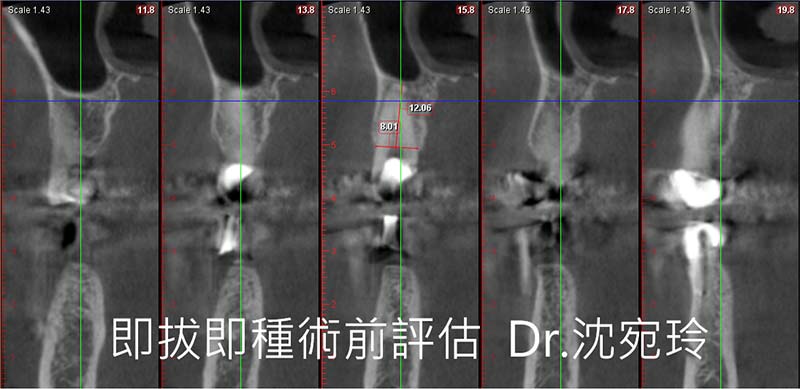

即拔即種的case,是需要慎重篩選的,首先原始牙根條件、牙周條件需要有骨本。評估可讓植牙卡住的骨本足不足夠,從2D影像和3D電腦斷層都應審慎評估。

此次的案例為即拔即種,除了拔牙前X光片的審慎評估,還有拔牙時使用特殊器械,致力於保存頰側骨板和拔牙窩的完整度!!讓勝算多一籌!!